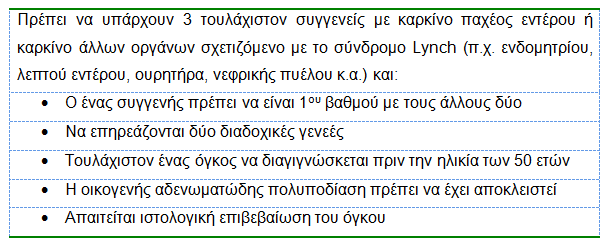

- Για τη διάγνωση του HNPCC εφαρμόζονται τα κριτήρια του Άμστερνταμ (Πίνακας 5).

- Στην περίπτωση καρκίνου που πληρεί τα κριτήρια αυτά, γενετικός έλεγχος για μικροδορυφορική αστάθεια διενεργείται στα μέλη της οικογένειας του προσβεβλημένου ατόμου και αυτά πρέπει να υποβάλλονται σε κολονοσκόπηση επιτήρησης από νεότερη ηλικία.

- Η συμπαρουσία εξωκολονικών καρκίνων συνιστά το σύνδρομο Lynch II (Πίνακας 6).

Πίνακας 5.

Κριτήρια του Άμστερνταμ για τη διάγνωση του κληρονομικού μη πολυποδισιακού καρκίνου του παχέος εντέρου (HNPCC, Σύνδρομο Lynch)